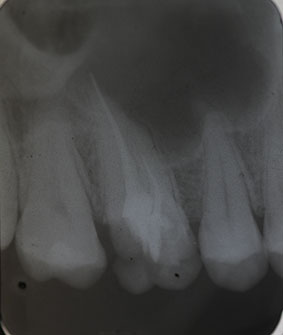

Nach Darstellung aller Wurzelkanaleingänge wird in einem zweiten Schritt das frakturierte Wurzelkanalinstrument dargestellt (Abb. 3 u. 4). Hierfür verwenden wir den Aufsatz 3E des Tigon+. Durch die schmale und lange Form des Instruments erreichen wir einen tiefen und schmalen Zugang.